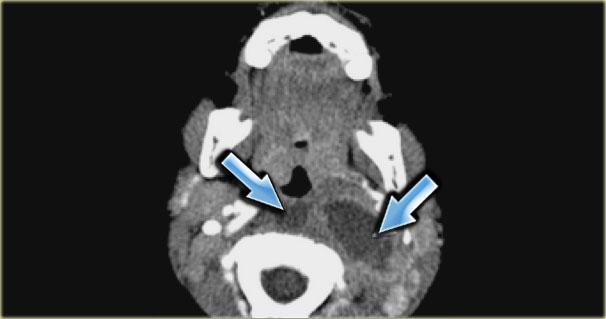

Paraganglioma: Hình ảnh MRI chuỗi xung T1W có tiêm thuốc tương phản từ Gadolinium tại mức thanh quản trên thanh môn

Paraganglioma

Bước 1: Xác định khoang

Bên trái là hình ảnh một bệnh nhân có khối sưng ở bên trái cổ.

Hãy quan sát hình ảnh MRI tại mức thanh quản trên thanh môn và xác định tổn thương nằm trong khoang nào.

Sau đó tiếp tục đọc.

Khối sưng nằm tập trung giữa động mạch cảnh ngoài và động mạch cảnh trong.

Lưu ý rằng các mạch máu này bị chèn ép.

Rõ ràng tổn thương này phải nằm trong khoang cảnh.

Cần lưu ý rằng có một tổn thương nhỏ hơn nhưng có hình thái tương tự, nằm ở khoang cảnh bên phải.

Paraganglioma thường gặp dạng đa ổ ở 3% đến 5% bệnh nhân nói chung và 20% đến 30% ở những người có tiền sử gia đình dương tính.

Các tổn thương này ngấm thuốc mạnh trên CT và MRI như được thấy trên hình ảnh MRI mặt phẳng coronal sau tiêm Gadolinium này.

Trong tổn thương lớn hơn ở bên trái, có thể thấy các vùng mất tín hiệu dòng chảy điển hình (xem thêm hình ảnh mặt cắt ngang).

Vì vậy, chúng ta có thể kết luận rằng có các tổn thương ngấm thuốc mạnh hai bên với hiện tượng mất tín hiệu dòng chảy trong khoang cảnh, nhiều khả năng nhất là u thể cảnh hoặc paraganglioma.